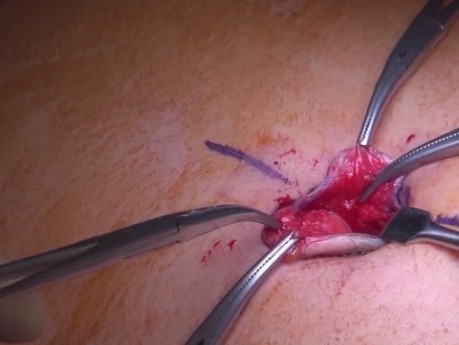

Cierre de perforación: el arte del clipado

Un caso de perforación incompleta tras procedimiento endoscópico en colon transverso. Se utilizaron hemoclips, suturando completamente el lecho de resección. El paciente comenzó a recibir antibióticos...